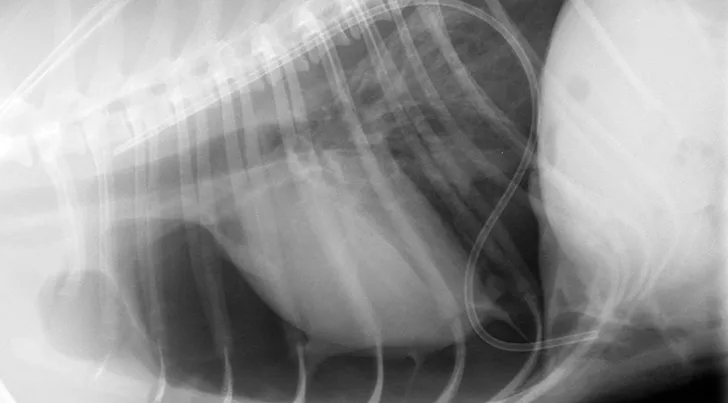

FIGURE 6

Lateral postoperative image documenting reduction of abdominal contents back into the abdomen and appropriate herniorrhaphy. Residual pneumothorax was apparent in this radiograph and was subsequently evacuated with the thoracic drainage catheter.